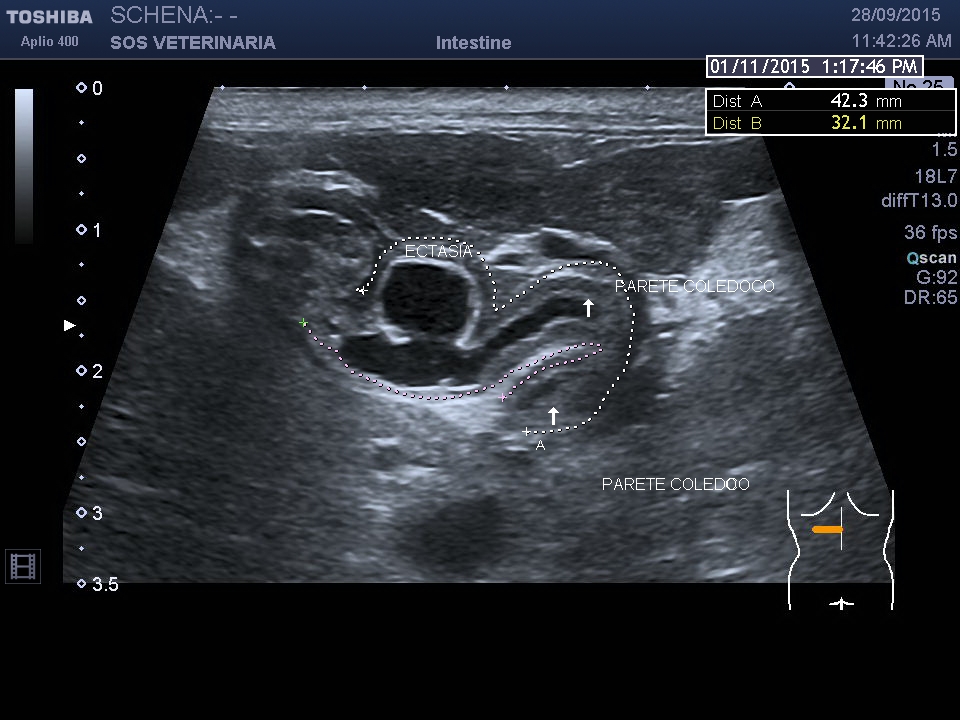

PROCESSO INFIAMMATORIO COLEDOCO E COLECISTE FORMAZIONE DI UN DIVERTICOLO ED ECTASIA DOTTO PANCREATICO

Gatta comune europea vive fuori e dentro casa pportata alla visita per anoressia e depressione rilevato ittero clinico

evidente la dilatazione e l’ispessimento   della parete  a carico di coleciste e coledoco con   formazione presfinterica di un ampolla ectasica simil diverticolo probabilemente secondaria alla cronicita’ del processo ,non si evidenziano ostacoli calcolotici o neoformazioni occludenti  il deflusso intra o extraluminali e a livello della papilla , il pancreas si presenta omogeneo ipoecogeno iperplastico trama vasale  ben evidenziabile .

Una  terapia di lunga durata con prednisolone alla dose di 0,5 mg/Kg sid comninata con marbofloxacillina e metronidazolo ha portato  dopo 4 settimane a risoluzione clinica e di laboratorio e ad un notevole miglioramento dell’imaging ,permane a distanza di 2 mesi  l’ectasia del dotto pancreatico e mofificazioni preampollari del coledoco con grado di distensione molto ridotto. Si e’ concluso  per un processo infiammatorio  possibile complesso colagioepatie ibd pancreatite (triatide)  con fenomeni iperplastici e fibrotici  a livello della papilla duodenale  e stenosi parziale del deflusso intraparietale duodenale ,tuttavia l’assenza di esami istopatologici non permette conclusioni certe eziopatogenetiche se non le evidenze riscontrate durante il decorso. Dopo due mesi il paziente alla sospensione dei farmaci mantiene la remissione.